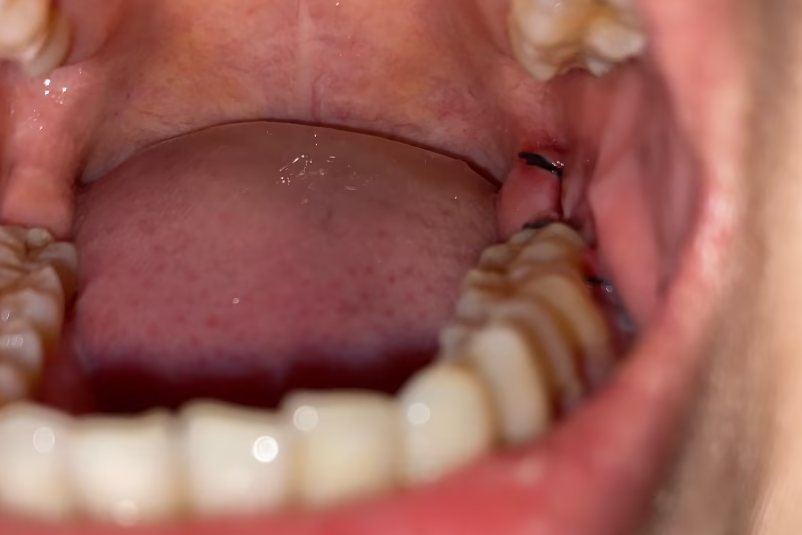

拔智齿缝针处白色一坨可能为正常的肉芽组织或伤口继发感染。

肉芽组织是牙龈愈合过程中的正常增生物,为颗粒状的新生组织。缝线出伤口继发感染可出现局部红肿,有白色坏死组织。

拔智齿缝线处愈合会出现粉红色、乳白色新鲜的牙龈组织生长,填补于伤口愈合处。肉芽组织血管丰富,表面呈颗粒状,一般无疼痛感。

拔智齿缝线伤口继发感染时局部牙龈会出现充血、水肿,伴有疼痛,伤口表面会形成糜烂或溃疡,出现白色坏死组织或脓性分泌物覆盖。